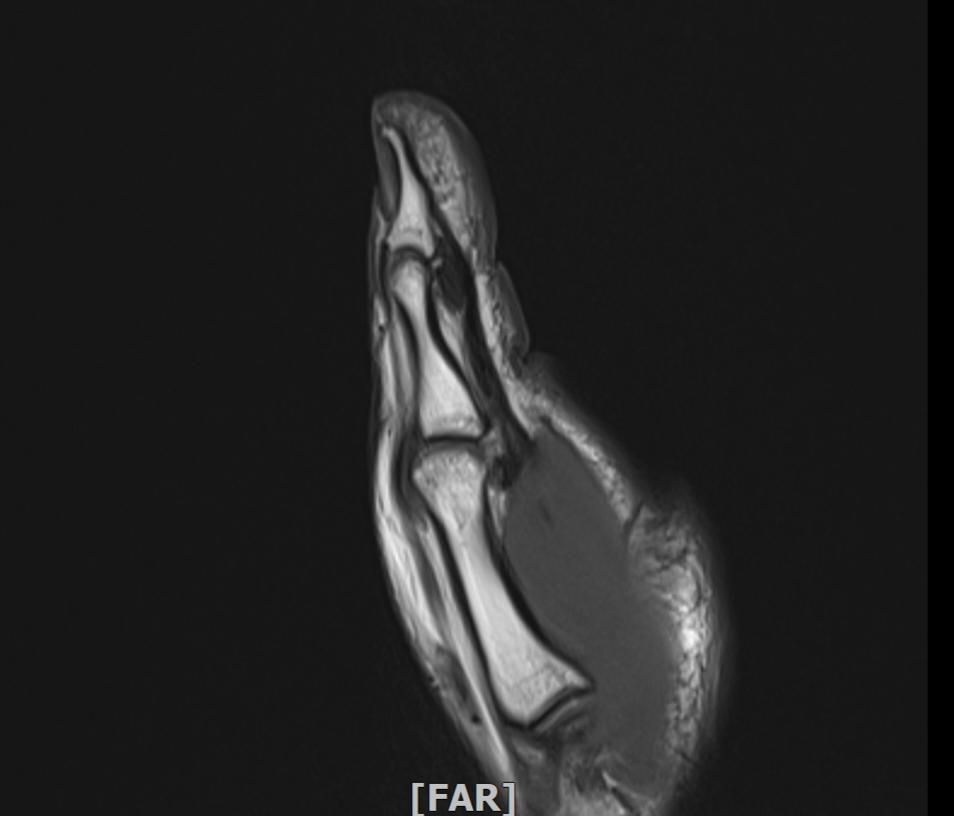

mri 엄지손가락 미세골절 여부확인

공구에 왼손이 말려서 엄지를 다쳤습니다 응급실에서 부목고정 조치후 이틀후 mri촬영 하였습니다.

엄지손가락 뼈가 자주 욱씬거리는데 미세골절 여부 확인 부탁드립니다.

• 1번 째 사진

우선 현재로썬 MRI 사진으론 정확한 판단을 하긴 어렵지만 주변 연부조직의 손상이 보여집니다.

다만 미세골절 같은 경우는 여러 방면의 판독이 필요하므로 정확한 판독은 병원에 내원하셔서 MRI 촬영을 한 병원에 판독지를 받으시고 전문의에 판독을 받으시길 적극 추천드립니다.